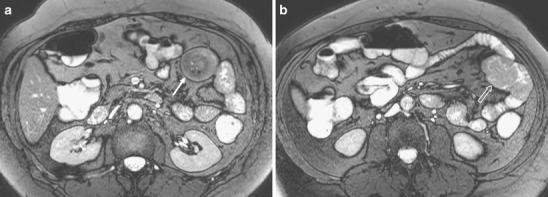

We present a spectrum of less common and less well-known bowel and mesenteric diseases (e.g. internal hernia, intussusception, neuroendocrine tumour) from our small bowel MR database of over 2,000 cases.

These diseases can be found in patients referred for bowel obstruction, abdominal pain or rectal blood loss. Further, in patients with (or suspected to have) Crohn's disease, some of these diseases (e.g. neuroendocrine tumour, familial Mediterranean fever) may mislead radiologists to erroneously diagnose active Crohn's disease.

我们从 2000 多例小肠 MR 数据库中展示了一系列不太常见和不太知名的肠道和肠系膜疾病(如内疝、肠套叠、神经内分泌肿瘤)。

这些疾病可发生于因肠梗阻、腹痛或直肠出血而就诊的患者中。此外,在(或疑似患有)克罗恩病的患者中,这些疾病中的一些(如神经内分泌肿瘤、家族性地中海热)可能会误导放射科医生错误地诊断为活动性克罗恩病。